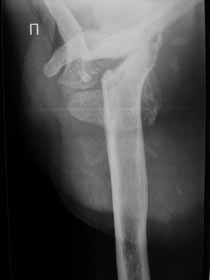

Не усмотрел в анамнезе "ноябре 2009 - травма с потерей сознания. В феврале 2010 г - первый рентген правого плечевого сутава - перелом анатомитеской шейки".

Поэтому желательно выставить все рентгенологические и данные МРТ для сравнения со снимками из статьи.

Думаю, коллеги будут не против увидеть рентген.

Извиняюсь, что-то фотографии сразу не прошли. сейчас исправимся.